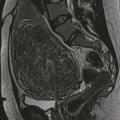

Les fibromes utérins sont les tumeurs les plus fréquentes de l’appareil génital féminin. Ils peuvent être asymptomatiques ou associés à différents signes cliniques. Dans certains cas, ils ont un rôle délétère sur la fertilité. Les modalités de traitement sont nombreuses, variables en fonction des signes cliniques, de la cartographie des myomes, du désir ou non de conserver l’utérus et du projet parental.